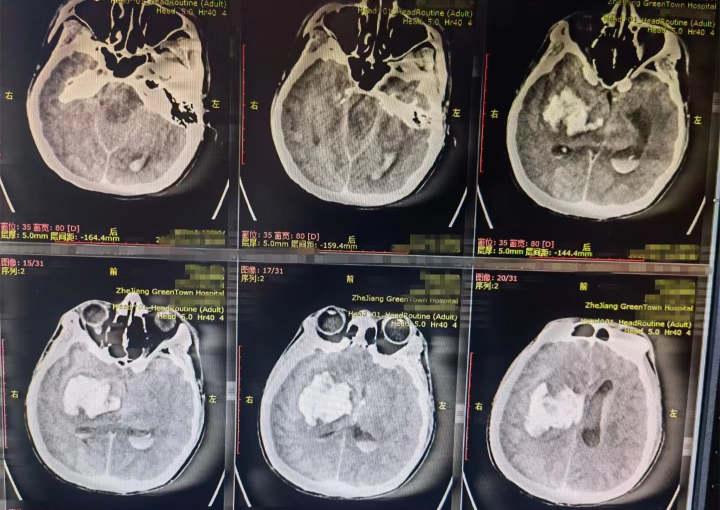

急诊科检查后发现小金血压高达182/137mmHg,右侧瞳孔散大,CT显示右侧基底节脑出血约50ml,脑干受压变形,超声提示双侧肾脏萎缩。神经外科主任周开顺立即带领团队进行了开颅血肿清除术,并开展床旁血滤。

周开顺主任在术中发现小金的脑血管畸形,出血量高达80ml,经过4个小时的手术,小金被送往ICU。后从小金父母口中得知,小金自己一人在杭工作,只听他说起肾脏不好、血压有点高,但具体情况他们也不得而知。